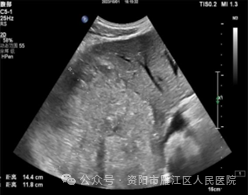

近日,56岁的李大叔因“右上腹疼痛20+天”入住我院。入院后查腹部增强CT:肝脏内结节、团块状稍低密度影,考虑肿瘤性病变。遂请超声科会诊, 腹部普通肝脏彩超提示:肝右叶实性占位,考虑肿瘤性病变可能。

超声造影:肝右叶实性占位性病变,考虑肝细胞Ca可能性大。

为进一步明确肝右叶病变的病理类型,遂行超声引导下肝肿物穿刺活检: